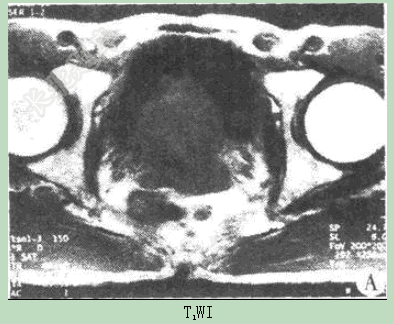

- 单项选择题患者男性,74岁,进行性排尿困难4月,MR图像如下,最有可能的诊断是( )。

D、前列腺癌